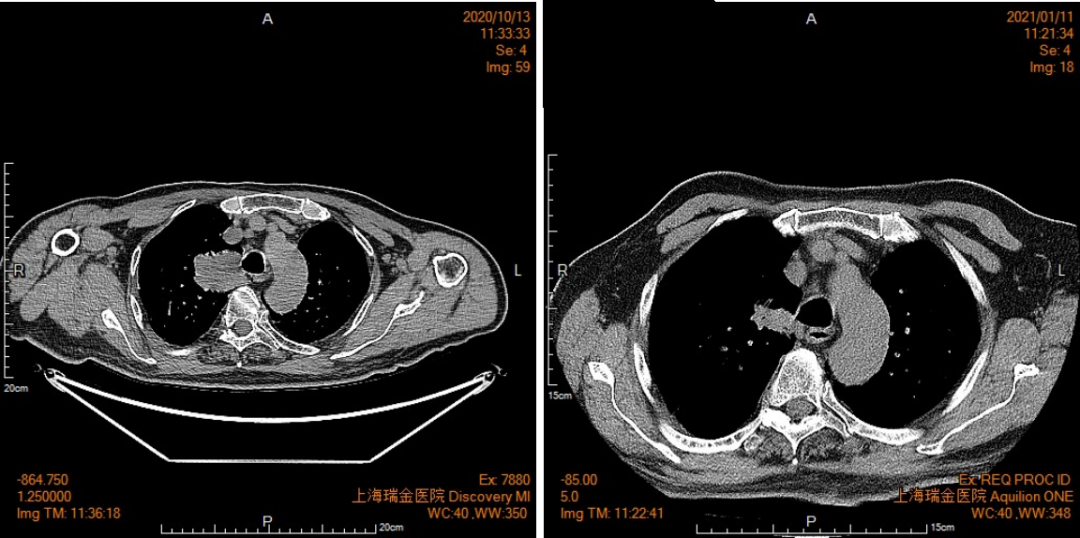

常见的咳嗽、气短,元凶竟是基因突变 91岁的汪先生(化名)因为反复咳嗽、胸闷气短,在外院治疗3个月不见好转,随后来到瑞金医院就诊。 为明确病情,瑞金医院呼吸与危重症医学科医生将他收入院,检查后发现汪先生的右肺上有团块影,右肺尖高代谢结节等问题,考虑转移性病变,原来咳嗽的元凶竟然是肺癌晚期。 为了精准治疗,医生对汪先生的活检病理组织进行了二代测序(NGS),竟然发现了罕见的基因突变MET-Y1003S点突变。 大家都知道,目前很多疾病都与基因变异有关。比如马凡氏综合征,是第15号染色体上的FBN1基因异常引起的,患者就像是小说中刀削般的面庞、柳腰不盈一握、青葱十指的真人版。 马凡氏综合征患者、特型演员Botet 肺癌也一样,多种基因变异使得正常细胞变成坏细胞,就是肿瘤细胞。而肺癌除了目前常规检测的肺癌九大驱动基因外,有时也会有其他少见及罕见基因参与。 MET基因在调节人体正常细胞的生长和发育中发挥重要作用。MET激活突变参与人体包括肺癌在内的多种肿瘤的发生。MET-Y1003S点突变是MET点突变的一种,此突变可能影响MET信号通路,参与肺癌的发生。 一项研究发现3%的肺腺癌样本中报告了MET突变。截止目前为止,全球仅在2019年Lung cancer杂志上报道过第一例MET-Y1003S点突变的肺腺癌患者。患者是一名61岁女性,没有吸烟史,因为体检发现CEA升高,进一步检查确诊肺癌,并且通过NGS检测发现携带MET-Y1003S点突变。而此次汪先生就是全球第二例肺腺癌患者携带MET-Y1003S点突变。 那么发现的汪先生的罕见突变对他的治疗有参考意义吗? 基因突变可以使得正常细胞变成坏细胞,所以针对突变的基因进行治疗,就可以阻止癌变进程。 但是,目前无针对MET-Y1003S点突变的特异性靶向治疗药物。瑞金医院呼吸与危重症医学科医生团队通过对目前已有的研究数据进行比对,结合在2019年 Lung cancer杂志的报道,即第一例MET-Y1003S点突变的肺腺癌患者在应用克唑替尼治疗后,1个月内被观察到病灶显著缓解,并且持续10个月以上。认为克唑替尼可能是对肺癌MET-Y1003S点突变患者具有临床获益的药物。 由呼吸与危重症医学科高蓓莉主任领衔的治疗小组经过充分讨论,以及和汪先生及其家属的认真沟通,对汪先生进行克唑替靶向治疗。经过2个月的治疗,汪先生的治疗评估结果令人震惊,他的肿瘤组织正在以惊人的速度消失中。 2020年10月(治疗前)CT 2021年1月(治疗后)CT 只有找对了钥匙,才能开启治疗之门。在汪先生本次肺癌诊治中,正是因为精准的基因诊断和对症治疗,才使得肺癌治疗如此成功。 #人物介绍 高蓓莉 肺癌、肺部感染和慢性阻塞性肺病等精准诊断现罕见基因突变